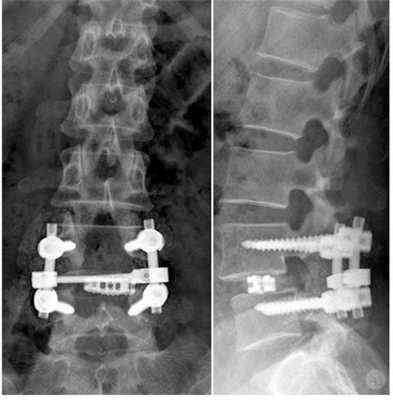

Стабилизационная система на рентгене.

В большинстве случаев проблемный сегмент стабилизируют с помощью металлоконструкций, чаще представленных транспедикулярными системами и пластинами с винтами из высокотехнологичных сплавов металла. В хирургии такая техника называется инструментацией позвоночника. Кроме металлоконструкций, для стабилизации также могут быть применены полимерные устройства, сделанные, например, из углеводородного волокна или резорбирующегося высокомолекулярного биополимера. К отдельной разновидности стабилизирующих вмешательств, которые не причисляют к инструментации, относят установку кейджей имплантатов межпозвоночных дисков.

Стабилизация поясничного отдела.